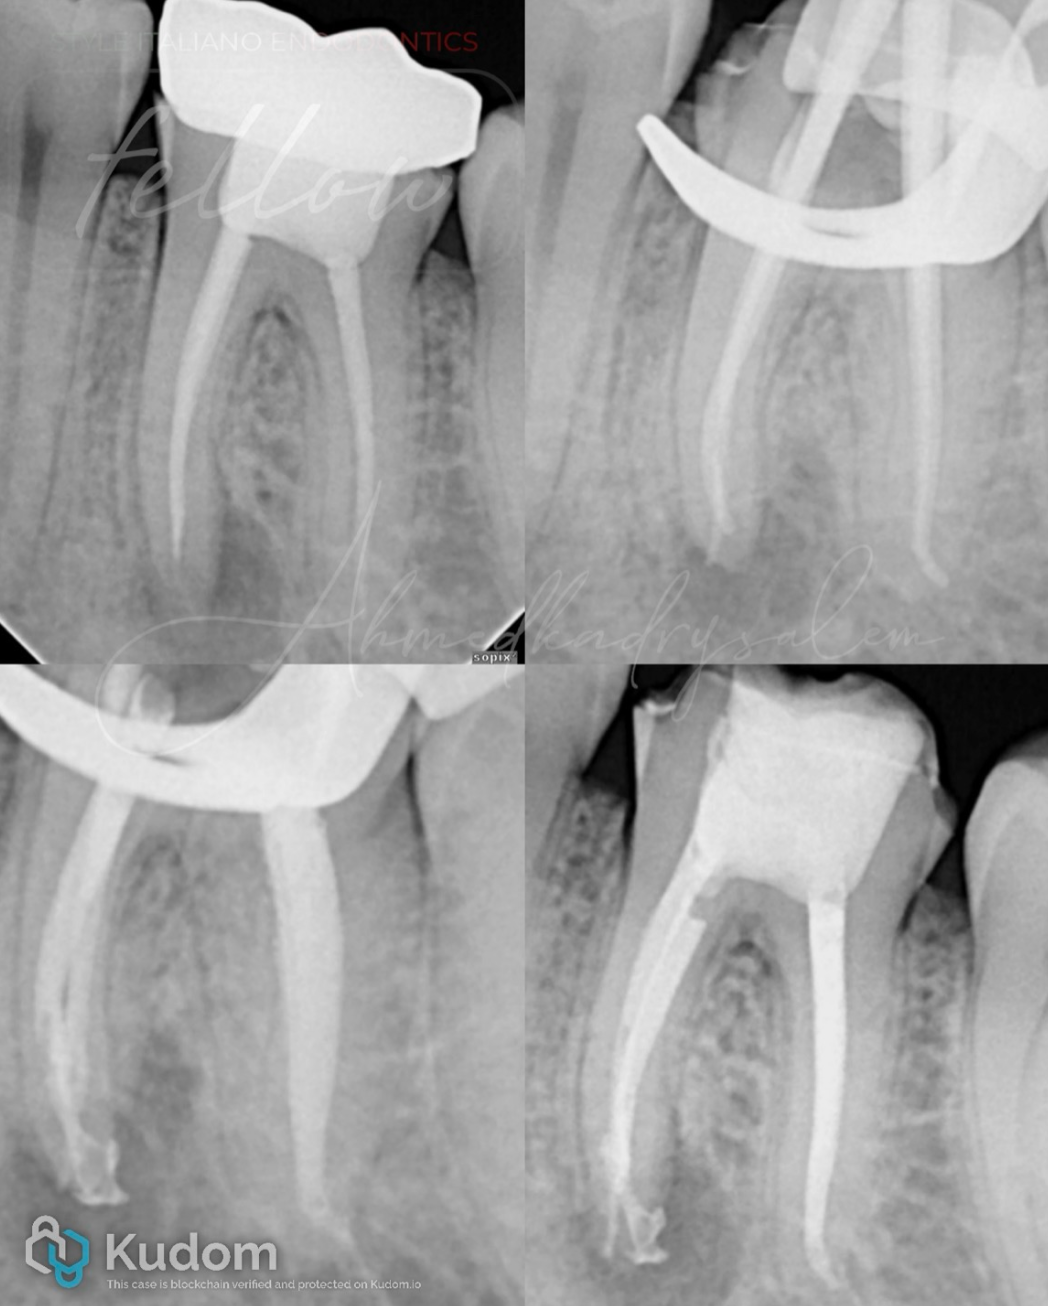

上图 8